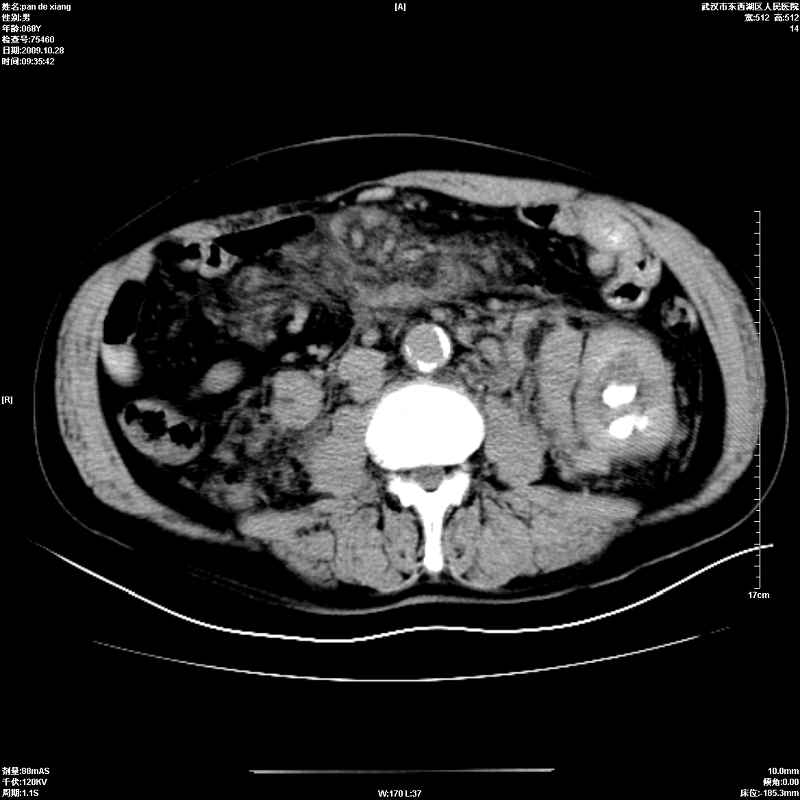

以下是引用杀毒软件在2009-10-28 20:41:00的发言:[br]结合临床考虑---白血病双肾改变或淋巴瘤。

以下是引用zxl51642在2009-10-29 9:59:00的发言:[br]结合临床“单克隆免疫球蛋白血症”,考虑双肾为继发损害并肾功能不全(尿中大量igg及少量iga、igm等大分子免疫球蛋白滤出所致继发损害),椎前软组织肿块为髓外造血。与浆细胞瘤有区别,平扫时有战友说的很清楚。